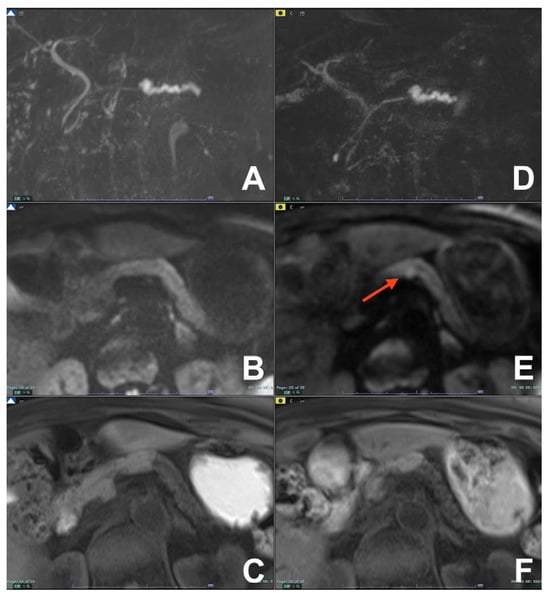

| Biliary leak after surgery or trauma | HASTE T2 | AXIAL | -- | -- | Anatomy and liquids analysis |

| INDICATIONS: MRI, thanks to the use of liver-specific MR contrast agents, can easily detect the site of bile leak. | HASTE T2 | CORONAL | -- | -- | Anatomy and liquids analysis |

| MRCP 3D | OBLIQUE CORONAL | -- | -- | Biliary anatomy and calculi | |

| GRE T1 IN/OUT | AXIAL | -- | -- | Steatosis | |

| GRE T1 3D DYNAMIC | AXIAL | Not necessary | YES high resolution | Useful for leak | |